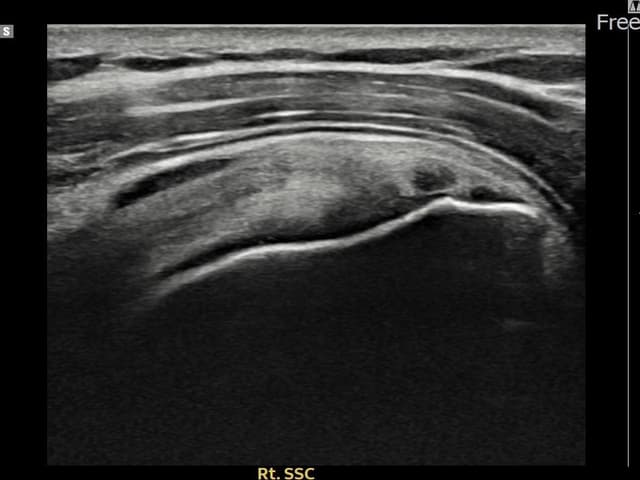

[촬영시기:23.11.28~24.02.06]

[어깨인대 축소봉합술] 우측 어깨 후방 통증과 팔을 바깥으로 돌릴 때 통증이 심해 내원하셨습니다.